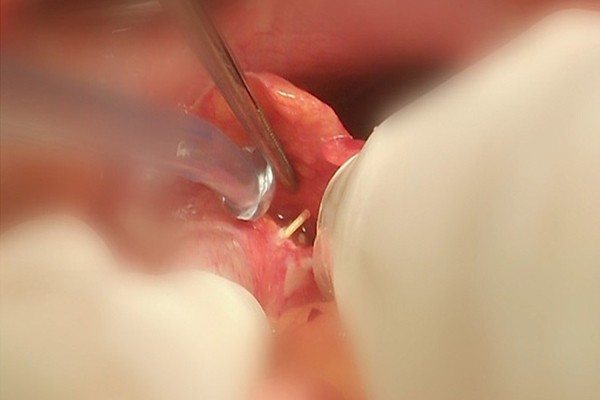

Ngay trong đêm, BS Dũng cùng ekip mổ cấp cứu cho bệnh nhân. Khi mở ra phát hiện toàn bộ đại tràng bị bầm dập có nhiều lỗ thủng do tăm đâm, ổ bụng có nhiều mủ.

“Với những trường hợp bị hoại tử đại tràng phải, bác sĩ sẽ phải cắt đại tràng rồi làm hậu môn nhân tạo. Tuy nhiên do thể trạng bệnh nhân tốt nên chúng tôi quyết định cắt một nửa đại tràng rồi nối thẳng với hậu môn”, BS Dũng thông tin.

Trong các vị trí do tăm đâm, thủng đại tràng nặng nề và điều trị phức tạp hơn cả. Sau 1 tuần phẫu thuật, hiện bệnh nhân đã ổn định.